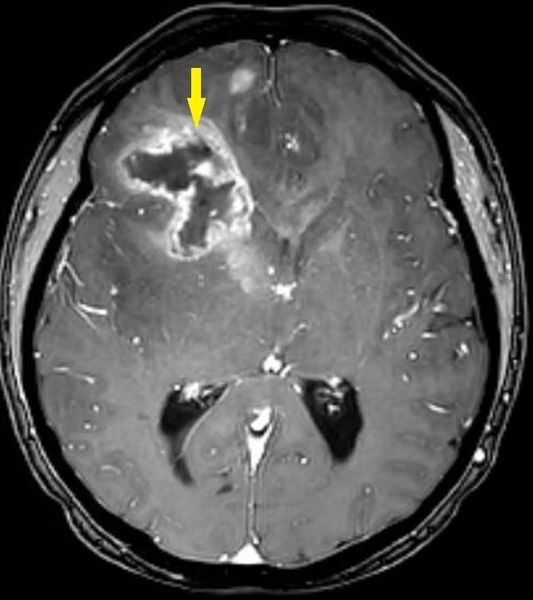

Наиболее информативный способ диагностики глиомы — это магнитно-резонансная томография (МРТ) головного мозга. Стандартом обследования пациентов с первичными опухолями центральной нервной системы является МРТ в режимах Т1 без контрастирования, Т2, Т2 FLAIR, Т1 с контрастированием либо в трёх проекциях, либо тонкими срезами в аксиальной проекции (в режиме SPGR). Этими методами можно наиболее точно определить расположение, размеры и структуру опухоли, а также её влияние на другие области головного мозга и магистральные сосуды [10].

Глиобластома на МРТ головного мозга [14]